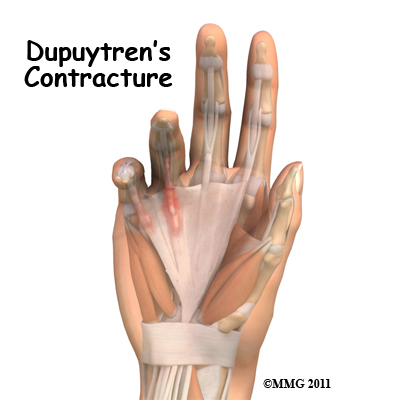

Dupuytrens Contracture Patient Guide

Dupuytren's contracture is a fairly common disorder of the fingers. It most often affects the ring or little finger, sometimes both, and often in both hands. Although the exact cause is unknown, it occurs most often in middle-aged, white men and is genetic in nature, meaning it runs in families. This condition is seven times more common in men than women. It is more common in men of Scandinavian, Irish, or Eastern European ancestry. Interestingly, the spread of the disease seems to follow the sa...